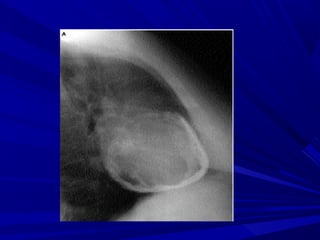

Radiological FindingsRadiological Findings

Normal <200mlNormal <200ml

Cardiomegaly >200mlCardiomegaly >200ml

+/- pleural fluid+/- pleural fluid

+/- pulmonary / mediastinal+/- pulmonary / mediastinal

- occasionally – small pulmonary infiltration or pleural- occasionally – small pulmonary infiltration or pleural

effusion (viral infection)effusion (viral infection)

- bacterial – in conjunction with pneumonia- bacterial – in conjunction with pneumonia